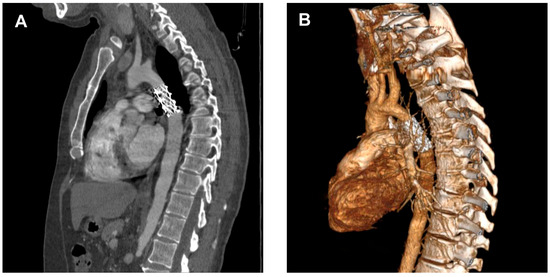

Diagnosis is often incidental, made during workup for hypertension or vascular complaints, and confirmed by imaging (CT—Figure 3, MRI, echocardiography) showing the atretic aortic segment and collateral vessels.

Angio CT (CT angiography) is typically performed at specific intervals after aortic coarctation repair with stent implantation to assess stent position, vessel patency, and rule out complications such as restenosis, aneurysm, or stent migration. Angio CT is usually recommended within the first 1–3 months after stent placement to verify correct stent expansion, position, and absence of immediate complications. After the initial scan, repeat angio CT or MRI is generally performed at 6–12 months after intervention to monitor for restenosis, vessel remodeling, or aneurysm formation. The choice between angio CT, MRI (preferred in younger patients due to lack of radiation), or echocardiography depends on age, stent type (metal artifacts), and clinical scenario [33] (Figure 5).